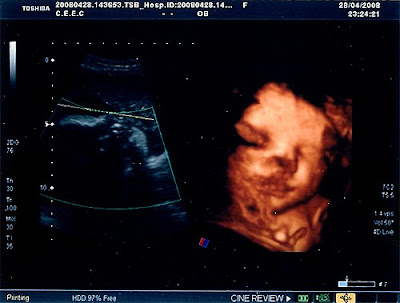

Ecografia das 32 Semanas

Finalmente fui fazer a última ecografia, a ecografia das 32 semanas.

Estivemos à espera imenso tempo, mais 2:30 do que devíamos, mas valeu a pena só facto de irmos ver a nossa pucunina, parecia que estava a sorrir para nós.

Está tudo bem ainda bem, o liquido amniótico, a placenta, o estar de cabeça para baixo já é normal, e ainda está contente de estar na barriga da mãezinha. Os factores importantes para se saber isso é o facto de se mexer muito, ter liquido suficiente, ver-se a caixa torácica a mexer-se muito bem, e os punhos fechados que significa que tem força.

A nível de peso é que não está muito pesada, no geral e por essa mesma razão está no percentil 25/50, mas a mãe também é pequenina, o obstetra prevê que nasça por volta de 3,100Kg, também não é necessário mais, ele deu-se por satisfeito com o resultado da ecografia. E como tivemos tanto tempo à espera tivemos direito a um bonús. Ora vejam.

P.S: Poderia ter ficado bem mais nítida se não tivesse com a carinha encostada à minha placenta.